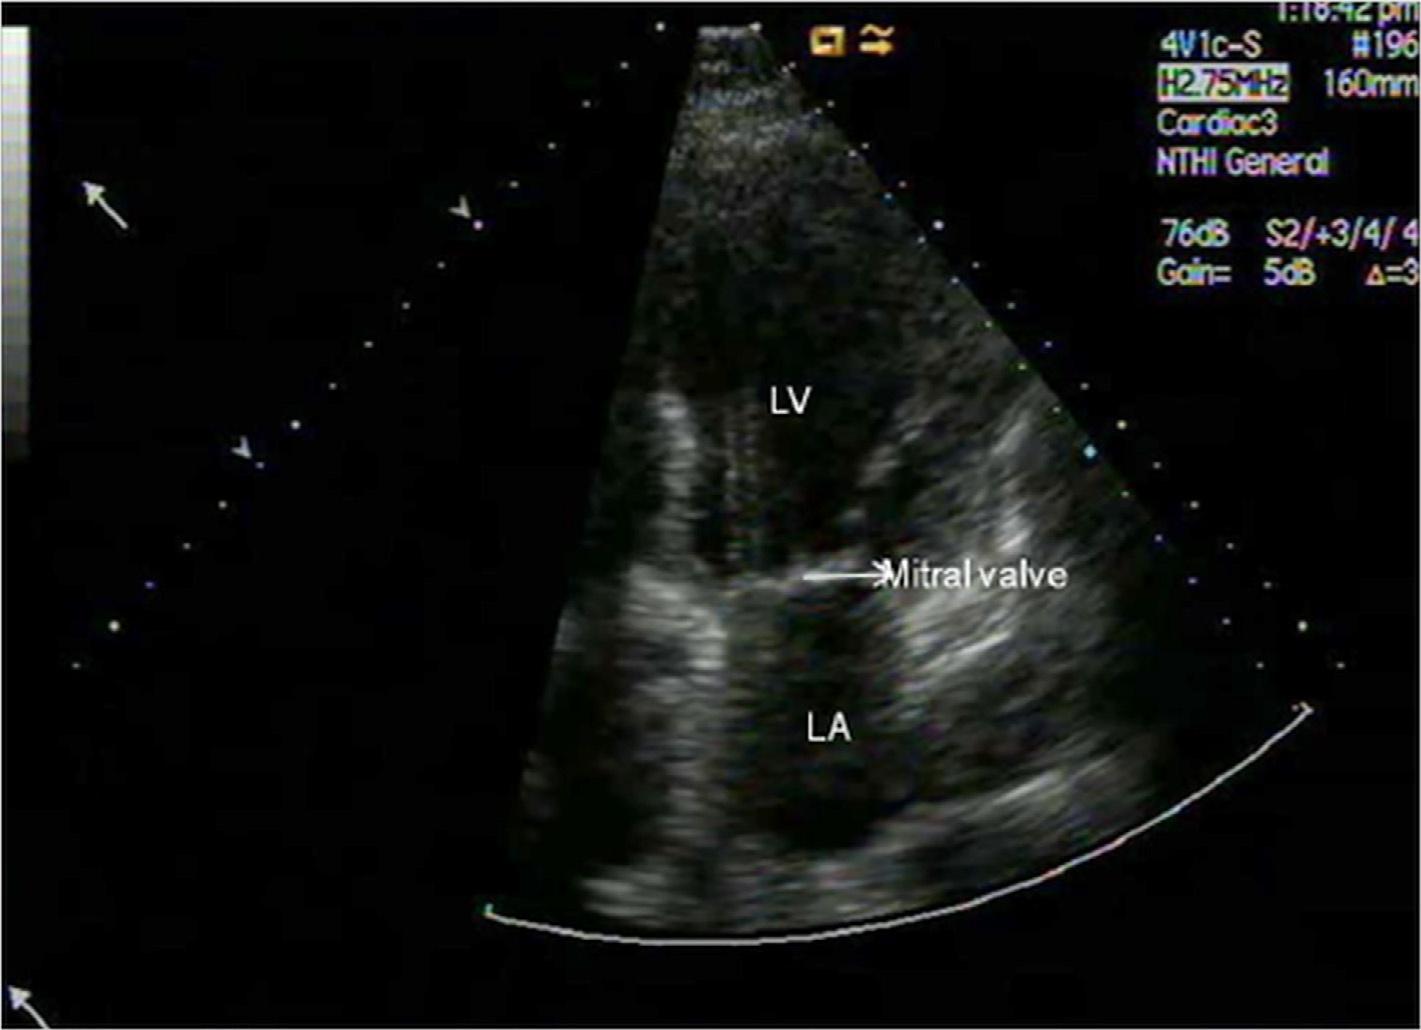

informationaboutcardiacanatomyandclinicalvalues.Thismakesechocardiographyamajordiagnostictool. Fig.1.4 showsanimageobtainedwiththehelpof2Dechocardiography.

FIG.1.4 Apical4-chamberviewofMVtakenwith2Dechocardiography.